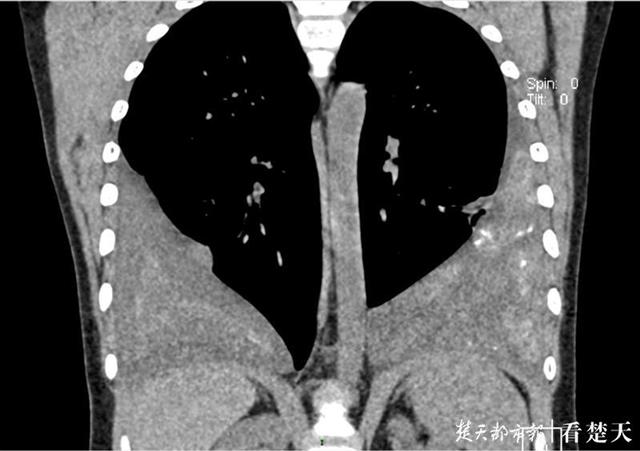

拍片发现,嘉嘉的肺部形态很是奇怪——像桃心的两半一样,中间被气管连接在一起,原本肺部下端则被不明物体所覆盖 。进一步检查发现,嘉嘉确实为肺吸虫感染 。

武汉儿童医院心胸外科主任皮名安介绍,正是肺吸虫感染导致孩子双侧肺都有严重的积液,积液在肺中不断沉积,积液中的蛋白质等物质沉积、钙化形成类似“纤维板”,附着于孩子肺部下端,形成了类似桃心的形状 。